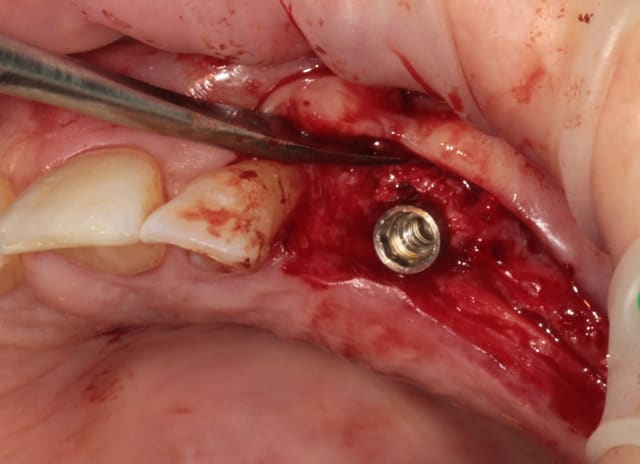

puis les Axioms avec un 4 mm en 25

retouche de l'os avec le D1 (face plane)

contrôle de l'os vestibulaire (différents contraste pour juger de la "minceur" de l'os :-)))